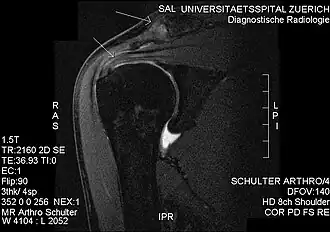

Plain x-rays of the shoulder can be used to detect some joint pathology and variations in the bones, including acromioclavicular arthritis, variations in the acromion, and calcification. However, x-rays do not allow visualization of soft tissue and thus hold a low diagnostic value.[2] Ultrasonography, arthrography and MRI can be used to detect rotator cuff muscle pathology. MRI is the best imaging test prior to arthroscopic surgery.[2] Due to lack of understanding of the pathoaetiology, and lack of diagnostic accuracy in the assessment process by many physicians,[21] several opinions are recommended before intervention.

Plain x-rays of the shoulder may show a “proximal humeral pseudocyst”. This localized area of bone atrophy is the result of increased blood circulation which demineralizes the bone at the attachment of the rotator cuff tendon. It is evidence of chronic inflammation of the rotator cuff. Chronic shoulder inflammation is frequently asymptomatic, and this cystic appearance may be the only evidence of an inflammation.[22][23]